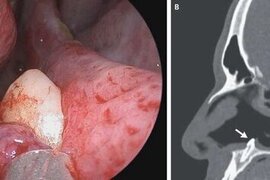

14 yaşlı qızın burnundan diş çıxardılar

Şərqi Sibirdə uşaq xəstəxanasının həkimləri tibdə nadir əməliyyatlardan birini icra edib. xəbər verir ki, 14 yaşlı pasiyentin burnundan diş çıxarılıb. Valideynlərin sözlərinə görə, burnun içində diş uşaq yaşlarından görülüb, amma uşağa heç bir təsiri yox idi. Lakin son aylar qız nəfəsalmada çətinli

17 iyun 2022